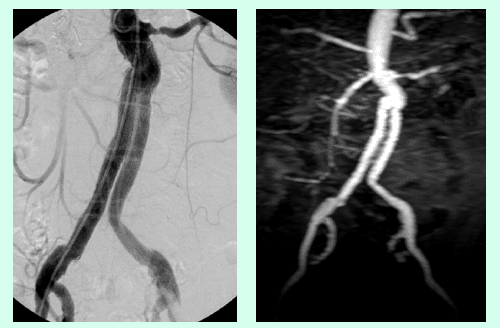

Abbildung A zeigt eine MR Angiographie der Becken-Bein-Arterien bei Patient:innen mit Verschluss der Aorta infrarenalis sowie der Beckenarterien beidseits. Es besteht ein Zustand nach Anlage eines axillofemoralen Bypass sowie Anlage einer Links-Rechts-Umleitung. Auch die Oberschenkelarterien sind beidseits verschlossen.

Abbildung B zeigt eine MR Angiographie der Becken-Bein-Arterien bei einem Patient:innen mit Zustand nach Anlage eines femoropoplitealen Bypasses rechts. Darüberhinaus besteht ein Aneurysma der linken A. poplitea.